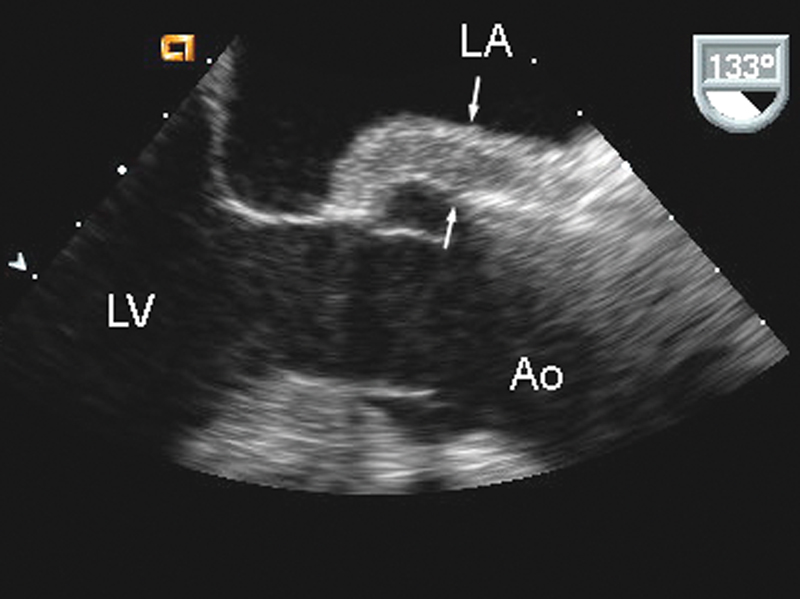

فحوصات تشخيصية لبعض امراض القلب والشرايين التاجية